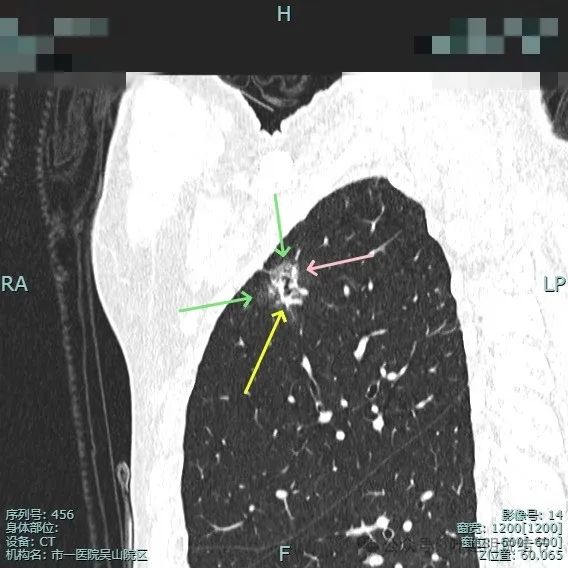

表面不平分叶,实性成分明显,灶内细支气管扩张。

此视角看是典型的浸润性腺癌影像表现:混合密度、毛刺锐利典型、表面分叶、边缘不平、灶内实性成分明显且整体显得杂乱、病灶内部明显扩张的细支气管,磨玻璃成分与正常肺组织之间边界清楚,整体轮廓也清楚。

血管进入以及胸膜牵拉,灶内小空泡征与密度显杂乱,次病灶也有血管进入。